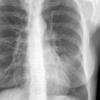

Case 2 Lingular pneum PA

Date: 04/17/2005

Views: 6414